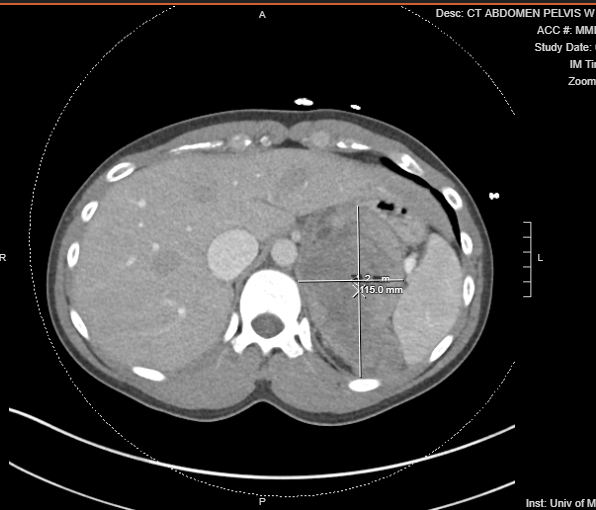

Luckily, there is a local-ish cash-pay imaging center within 1.5 hours of me. I was able to schedule my CT chest ordered by my new PCP. This cost me $272. I had this done about 6 weeks after my onset of symptoms on 2/26. By this time, I had about a 10-pound weight loss. I asked the tech who was imaging me if I could see the images. She could see that I was in my scrubs, so she asked me what I did. After the scan, she showed me the images. She pointed out several pieces of anatomy then pointed to a large structure and said, “I don’t know what that is.”